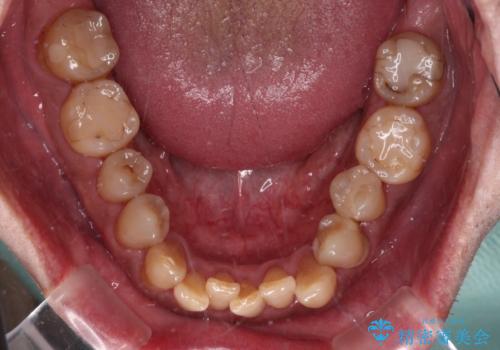

- 前歯のクロスバイトを気にして来院された患者様です。

40代男性で、インプラント補綴治療も経験されている方で、矯正治療をしても良いのかと悩んでいらっしゃいました。

下顎骨の左右のずれがあり、下顎全体が前方に出ている状態であったので、無理をせずにワイヤー装置にて矯正治療を行うこととしました。

クロスバイト改善には難儀しましたが、咬みやすく、笑ったときに清潔感ある口元に仕上げることができました。